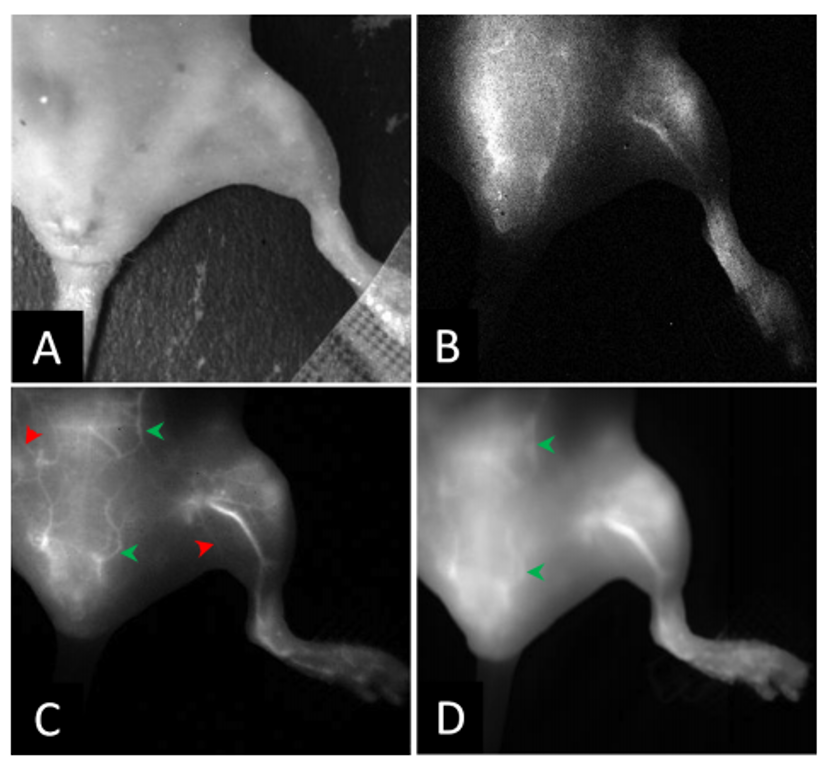

Raptor’s Ninox cooled Vis-SWIR camera helps advance medical imaging techniques.

Houston, Texas An exciting new paper published by one of our customers in the US highlights how the Ninox camera has helped advance in-vivo and in-vitro medical imaging. Zbigniew Starosolski and his colleagues in Children’s Hospital, Texas have been using our cooled InGaAs Ninox camera for several months, imaging in…